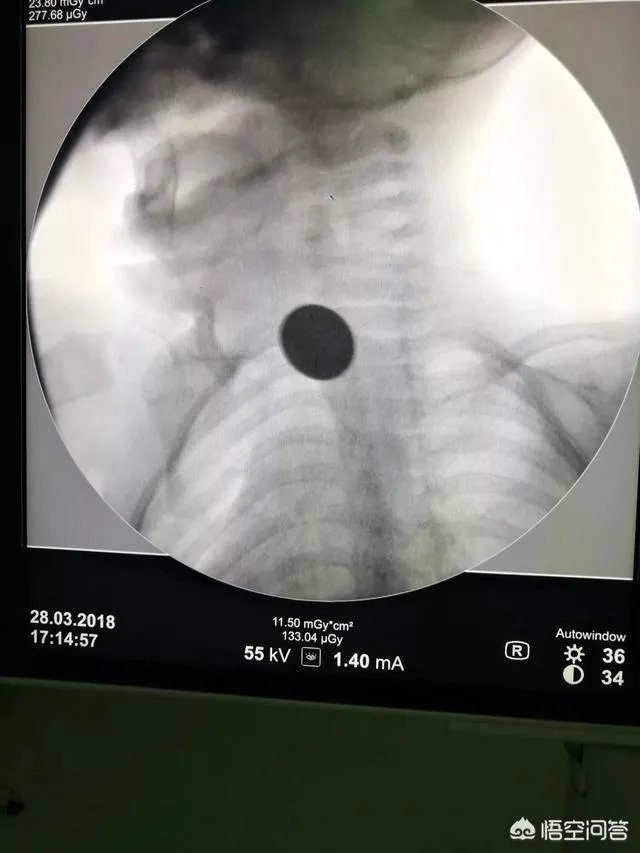

第二个病人是一个小孩子。那天中午我跟主任一起走路上班,进医院大门时碰到一个老奶奶抱着一个孩子大哭救命。我和主任跑过去一看,小孩子已经青紫,几乎没有呼吸,非常危急。从简短的交谈中知道孩子气管里卡东西了。主任抱起孩子跑去急诊科,命我赶快去拿气管插管的设备。我们科在9楼,我真是一口气跑上去,一口气跑下来拿来急救设备。到了急诊科及时把气管导管插进去。气管导管一插进气道,小孩子呼吸立刻好起来,嘴巴颜色也转红。最后卡住孩子气道的笔盖子被安全取出。说实话,如果当时孩子在大门口没有碰到我们,可能很难被救到。事后了解到孩子就住医院对面,父母和很多医院职工认识。孩子父母特地来医院感谢了好几次。

最后强调一遍,儿童气道异物和食道异物非常常见。大多是硬币,笔套,纽扣电池和花生瓜子,果冻等。父母尽量不要给孩子接触这些物品。万一出现气道异物可以使用海姆立克急救法办法(不建议没有经过训练的人员使用)。如果孩子呼吸困难,紧急送医。路上用力重拍儿童胸背上部(手掌拱起形成一个窝型)。如果没有呼吸特别困难,就尽量不要刺激小孩,平稳送医急救。